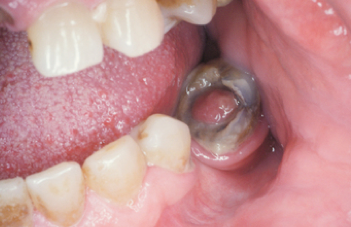

Pericoronitis

(Inflammatory process that arises within the tissues, surrounding the crown of a partially erupted tooth. Most commonly mandibular 3rd molars)